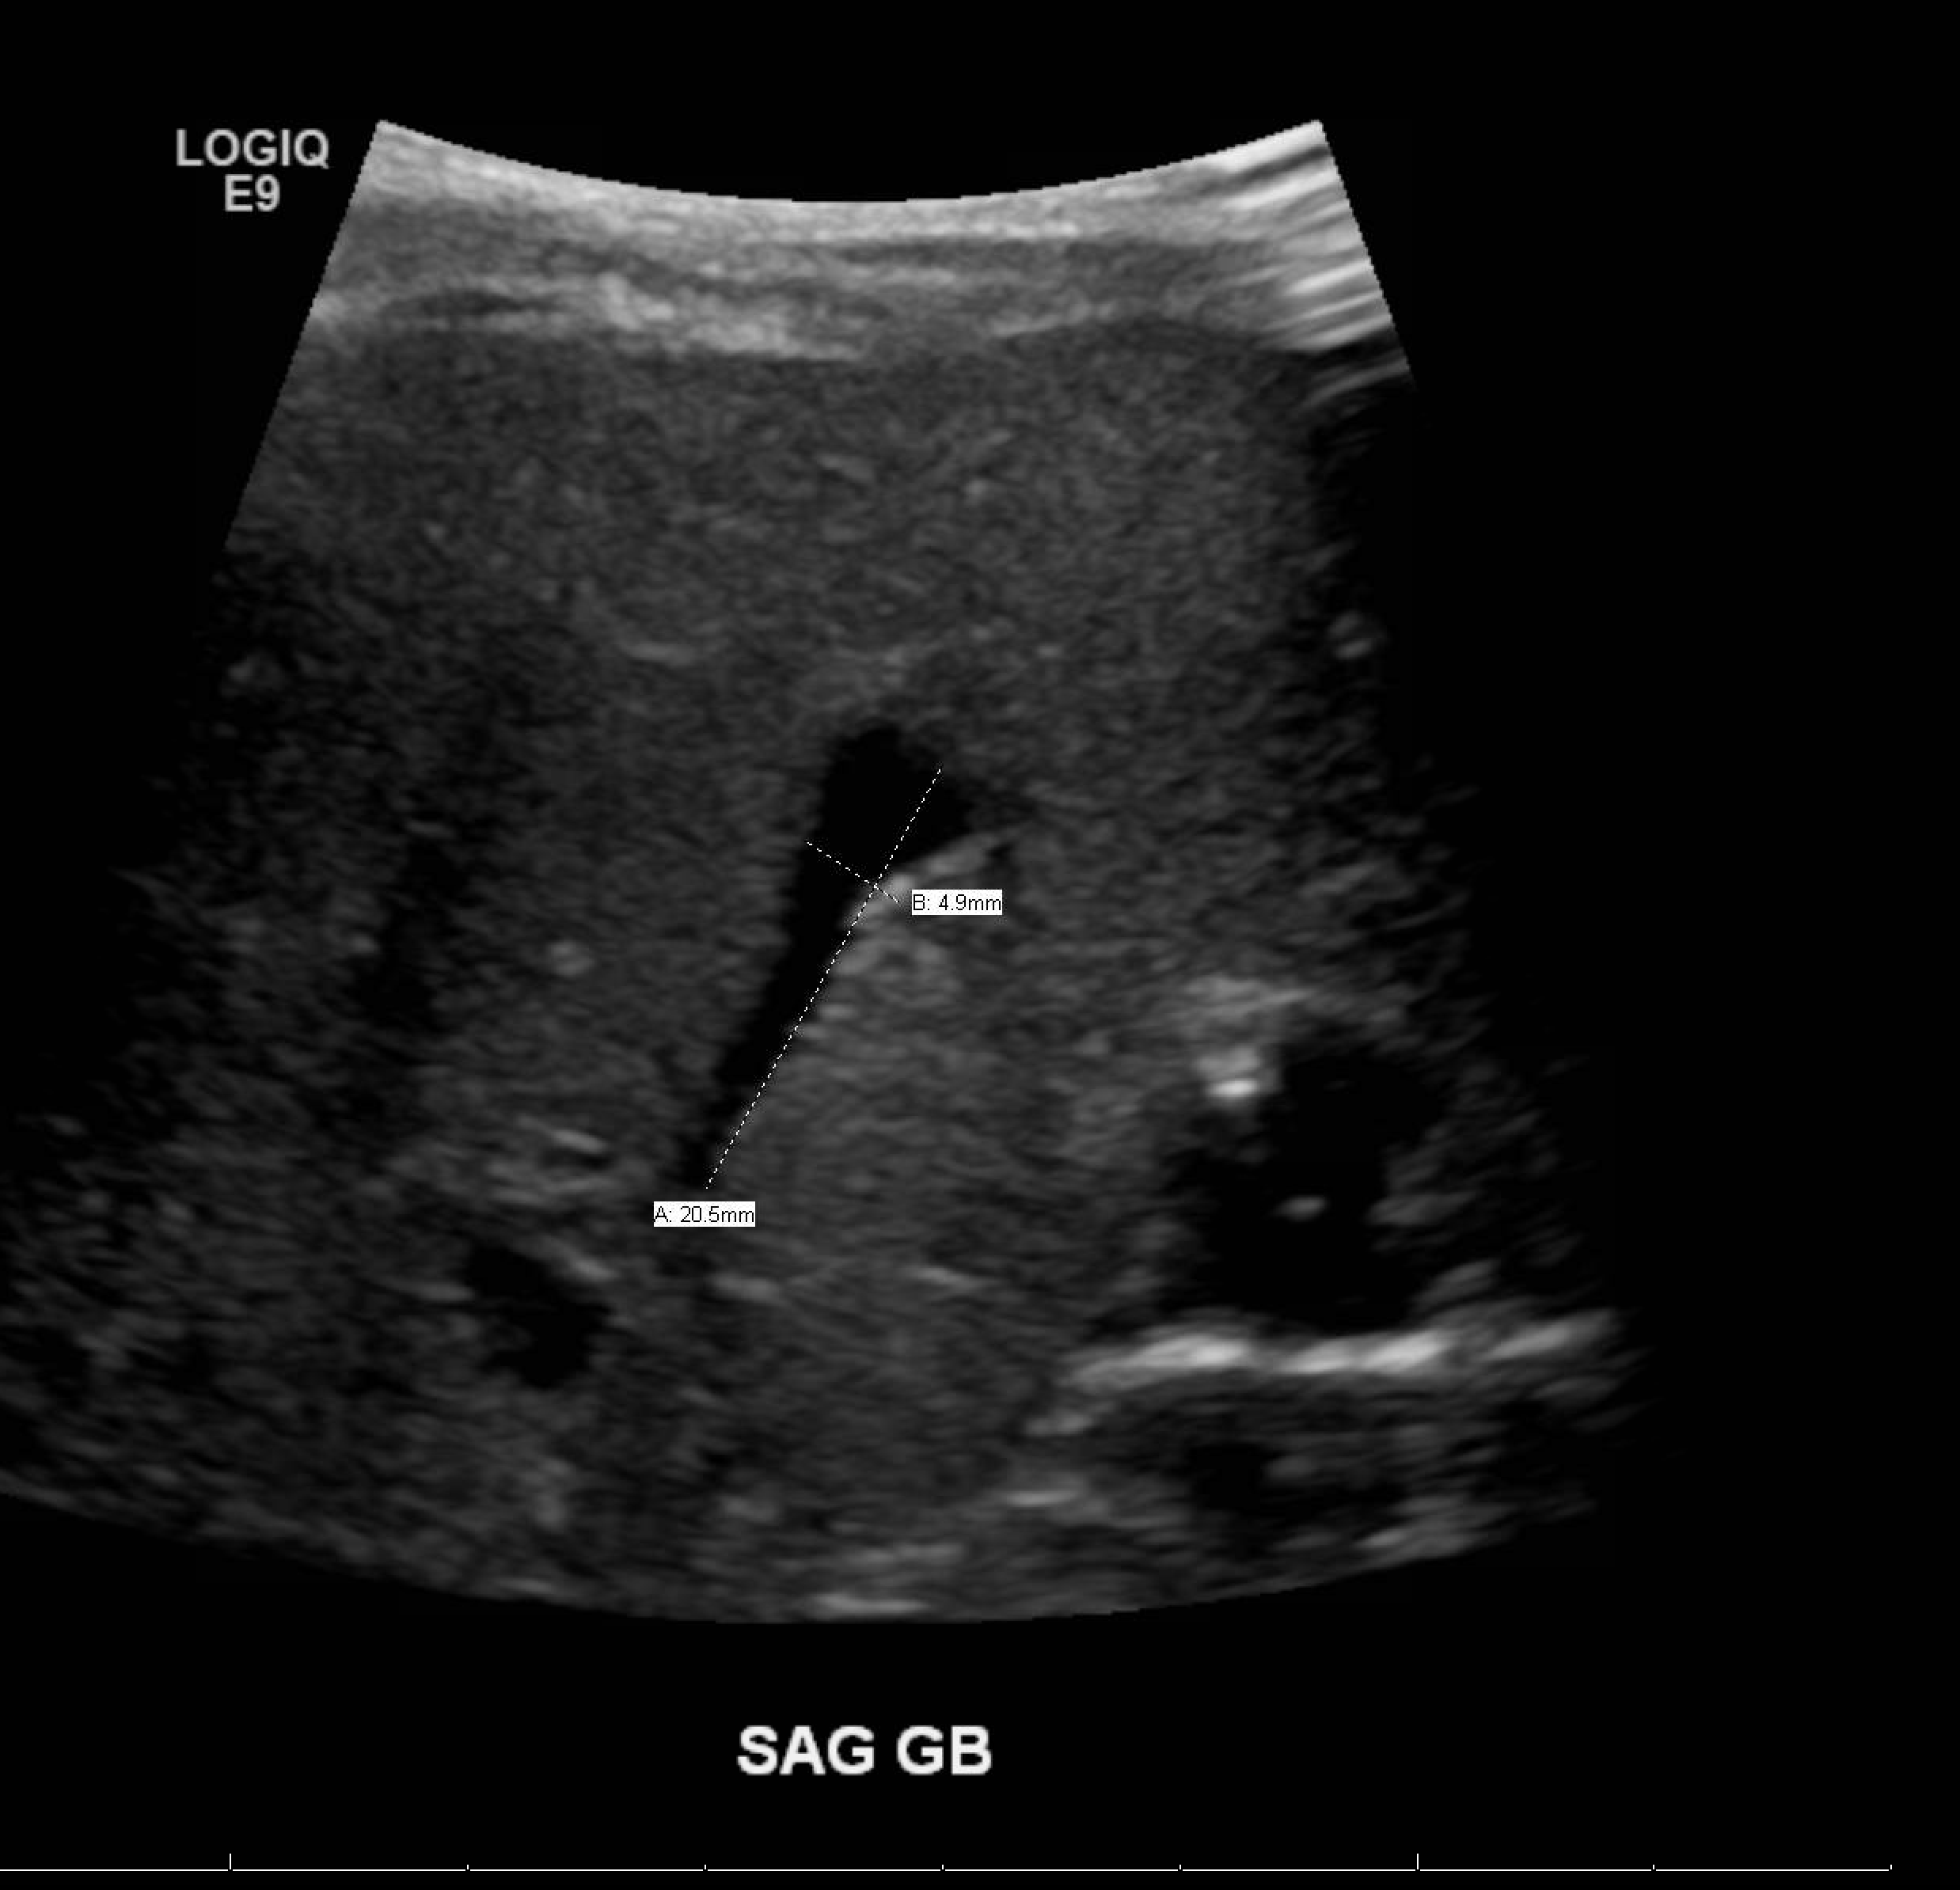

Age: 3 months

Sex: Male

Indication: Concern for biliary atresia

Radiotracer: Tc99m mebrofenin

Sample ReportAbsent biliary and bowel activity, which may reflect poor hepatic function versus biliary atresia.